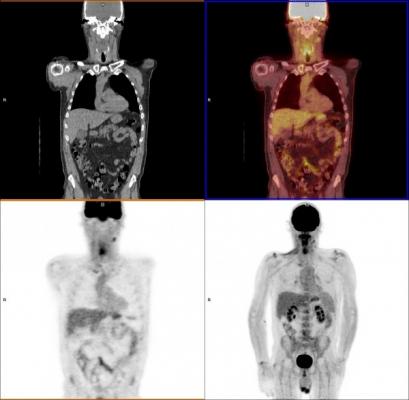

A PET-CT cardiac perfusion exam from a Siemens Biograph scanner. The black and white areas of the image show the CT imaging of the anatomy. The colored portion shows the PET overlay on the myocardium and is color-coded to show tracer uptake values. This can show areas of the heart muscle where there are perfusion defects cause by infarcts or coronary artery blockages due to a heart attack and help determine the severity of the ischemia.

A common question from patients is what is a PET-CT scanner? Today, most standalone PET imaging systems have been replaced by hybrid PET-CT scanners, which combine separate PET and CT imaging systems into one gantry to allow fused, simultaneous imaging using PET and X-ray CT. The CT system offers anatomical detail and helps with attenuation correction for the PET imaging for more accurate, clearer PET image reconstructions. The overlay of fused CT images on the PET scans can help pinpoint “hot spots” of tracer uptake, such as cancerous tumors. These can be used to help make a more accurate diagnosis, aid tumor monitoring or tracking during chemotherapy, and aid in either surgical or radiation therapy planning.

Most nuclear myocardial perfusion exams (which look for ischemia or infarcts in the heart muscle caused by heart attacks) use rubidium-82 (Rb-82). This is produced in a commercially available generator, where the active tracer can be produced on demand in the scanning room. The generator contains strontium-82, which decays into positron-emitting Rb-82. The use of these generators has made PET perfusion imaging feasible and more economical for imaging centers without cyclotrons.

PET is a primary imaging modality for the detection and tracking of cancer. Nuclear imaging (PET and SPECT) are also considered a standard of care for myocardial perfusion exams to see if there is a lack of blood flow to the heart muscle due to a heart attack. PET scans can also help detect and track neurological disorders in the brain, such as Alzheimer’s disease and evaluation of strokes.

Nuclear myocardial perfusion imaging (MPI) with PET and SPECT have been the gold standard for noninvasive detection of coronary ischemia and infarcts. However, the high radiation doses patients receive are making some providers think twice before referring their patients for nuclear MPI. Public concern over radiation risks from medical imaging have been brought to the forefront with numerous mainstream media articles in recent years.